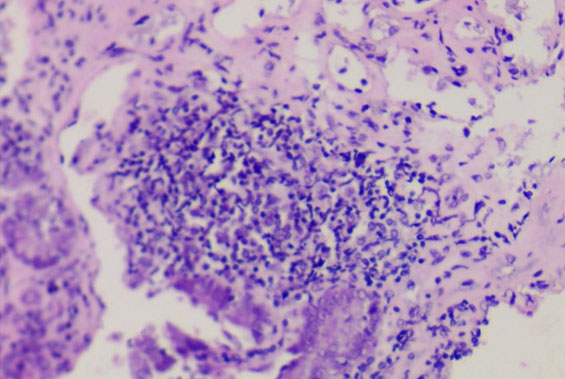

To evaluate a supposed reaction in the duodenal mucosa, biopsies of the proximal and distal regions were sent for histopathological analysis by H&E. In this analysis no signs of necrosis or granulation were observed, on the contrary, the tissue structure was preserved with the presence of a mild lymphocytic infiltrate (Figure 5).

Figure 5: Histopathology of duodenum showing the presence of lymphocytic infiltrate (200×, H&E).

To our knowledge this is the first report of a fungal biofilm on an IGB, in a patient conveying some signs and symptoms (gastric pain, nausea, malaise) possibly related to the presence of the biofilm and the inflammation found in the duodenum (Figure 5). We suggest this explanation as the classic diagnostic means in gastroenterology were not able to evidence the etiology of the symptoms presented by the patient. The iron deficiency anemia can also be associated with the presence of C. glabrata in the biofilm. The consumption of iron from the environment is one of the virulence factors described for this species [23].